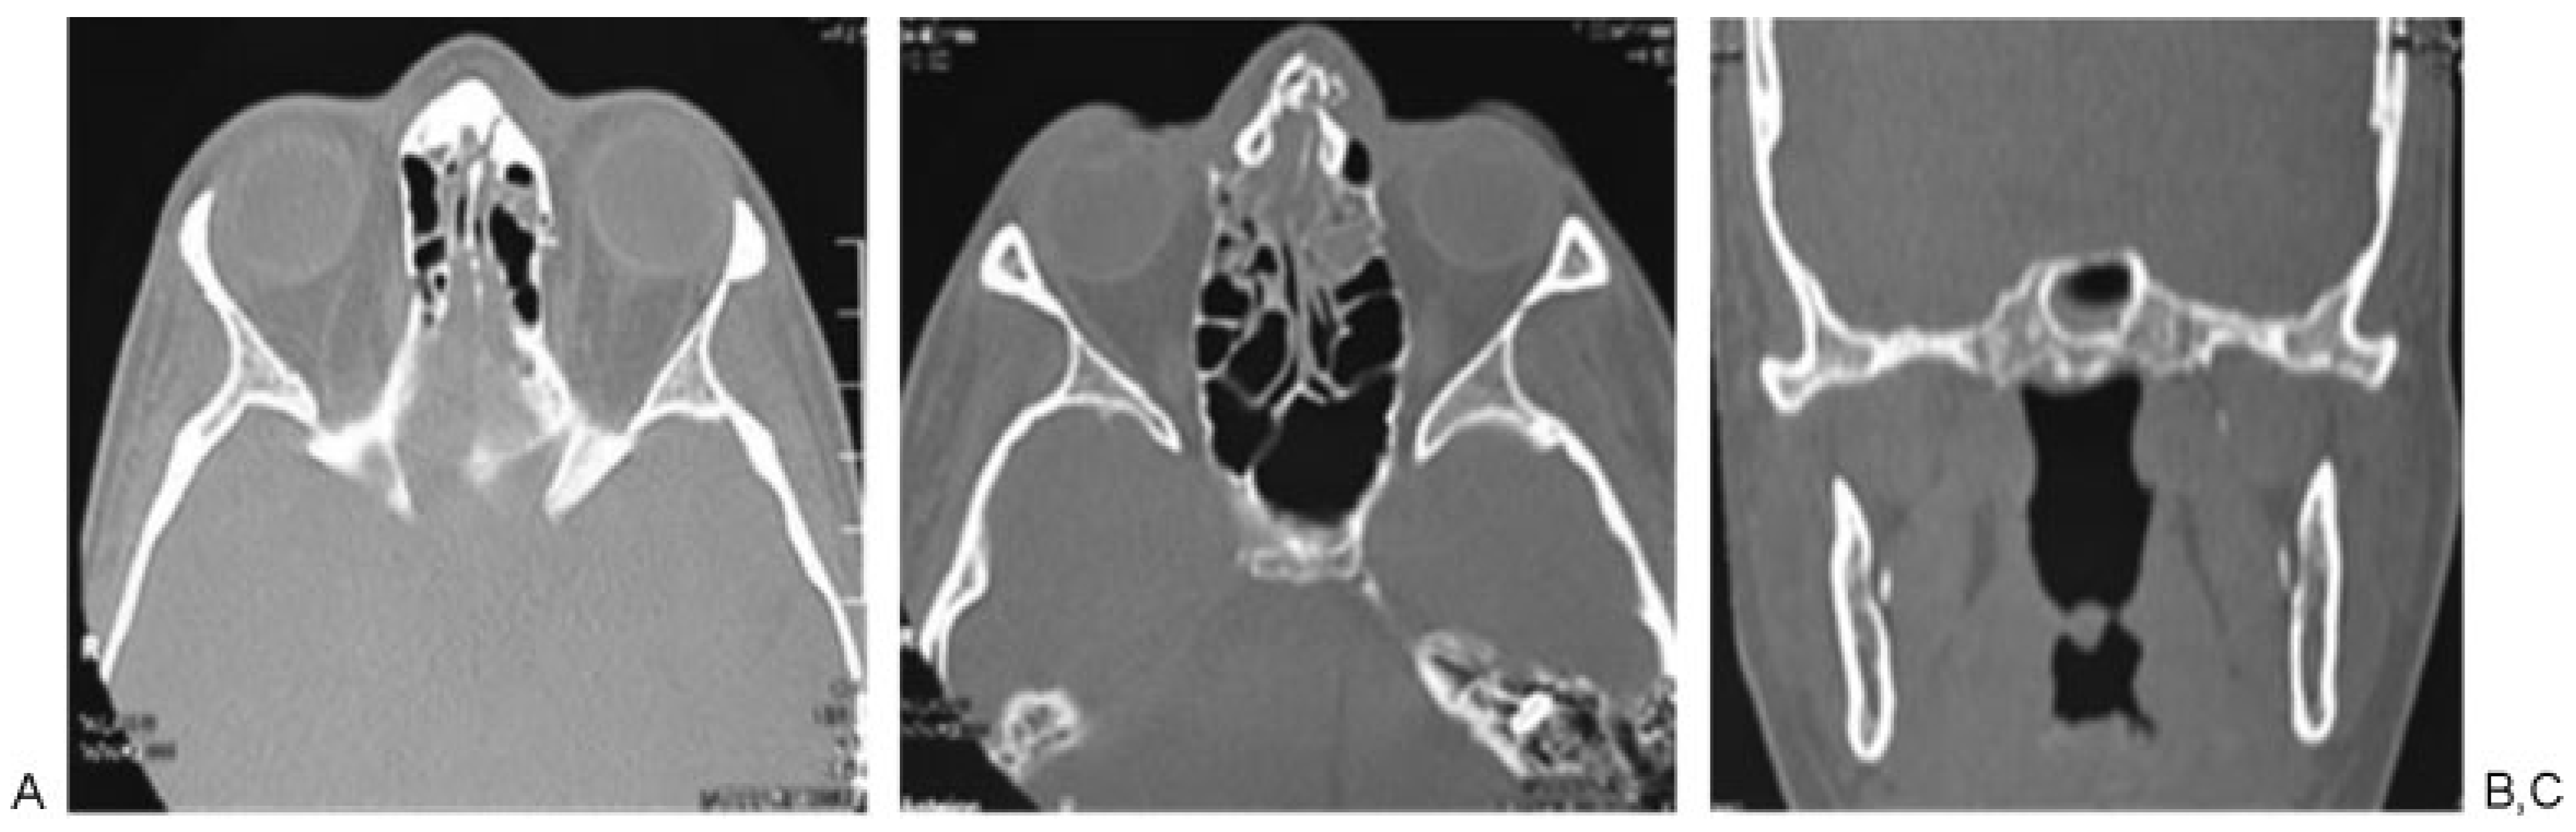

Figure 3. Patient 2: high-energy comminuted fracture of nasal bone (A and B), associated fracture of the sphenoid sinus.

According to Manson’s classification, 17.9% (n ¼ 38) of the trauma in the group corresponded to high-energy trauma, followed by medium-energy trauma at 33.5% (n ¼ 71) and low-energy trauma at 48.6% (n ¼ 103). Among the patients with high-energy trauma, 31.5% (n ¼ 12) had combined fractures of the sphenoid bone and sphenoid sinus and 31.5% (n ¼ 12) had sphenoid sinus fractures only. In contrast, 1.4% (n ¼ 3) of patients with middle-energy trauma had sphenoid bone fractures, 5.6% (n ¼ 4) of the patients had sphenoid sinus fractures, and 4.2% (n ¼ 3) of the patients had sphenoid bone and sphenoid sinus fractures. In the low-energy trauma group, only 1 patient presented sphenoid sinus fracture (0.97%; Table 3; Figure 2, Figure 3 and Figure 4).